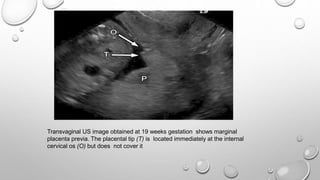

Transvaginal US image obtained at 19 weeks gestation shows marginal

placenta previa. The placental tip (T) is located immediately at the internal

cervical os (O) but does not cover it